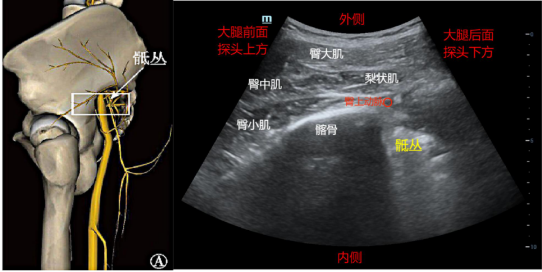

(二)侧路骶丛:短轴入路法,适合翻身困难的患者。

超声准备:低频探头,深度6-10cm。体位:平卧位。

解剖关键点:髂前上棘、髂骨、腋中线、坐骨大孔、臀大肌、梨状肌、股骨粗隆。

扫查方法:探头横向放置在平对髂前上棘水平髂骨翼下方,探头的前端位于腋中线位置,然后探头向尾端移动1-2cm左右,髂骨后半部分高亮回声声像消失时,即到达坐骨大孔的位置,解剖层次依次是皮下组织、臀大肌、臀中肌、臀小肌、梨状肌和髂骨,梨状肌内侧可见高回声的骶丛声像图。